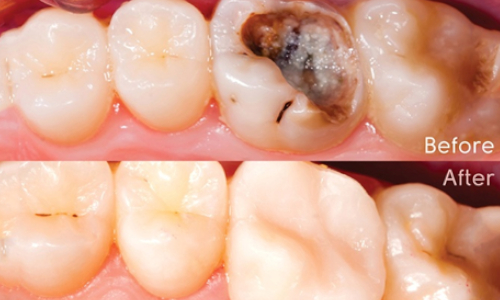

Steps in composite restoration

It is mostly completed in single sitting. Tooth appeared to be carious is prepared to receive composite. This procedure needs to be done in proper isolation to have good tooth to composite bond. After completion of the restoration, it is polished to get smooth and glossy surface so that there is no food retention.

In treatment of caries